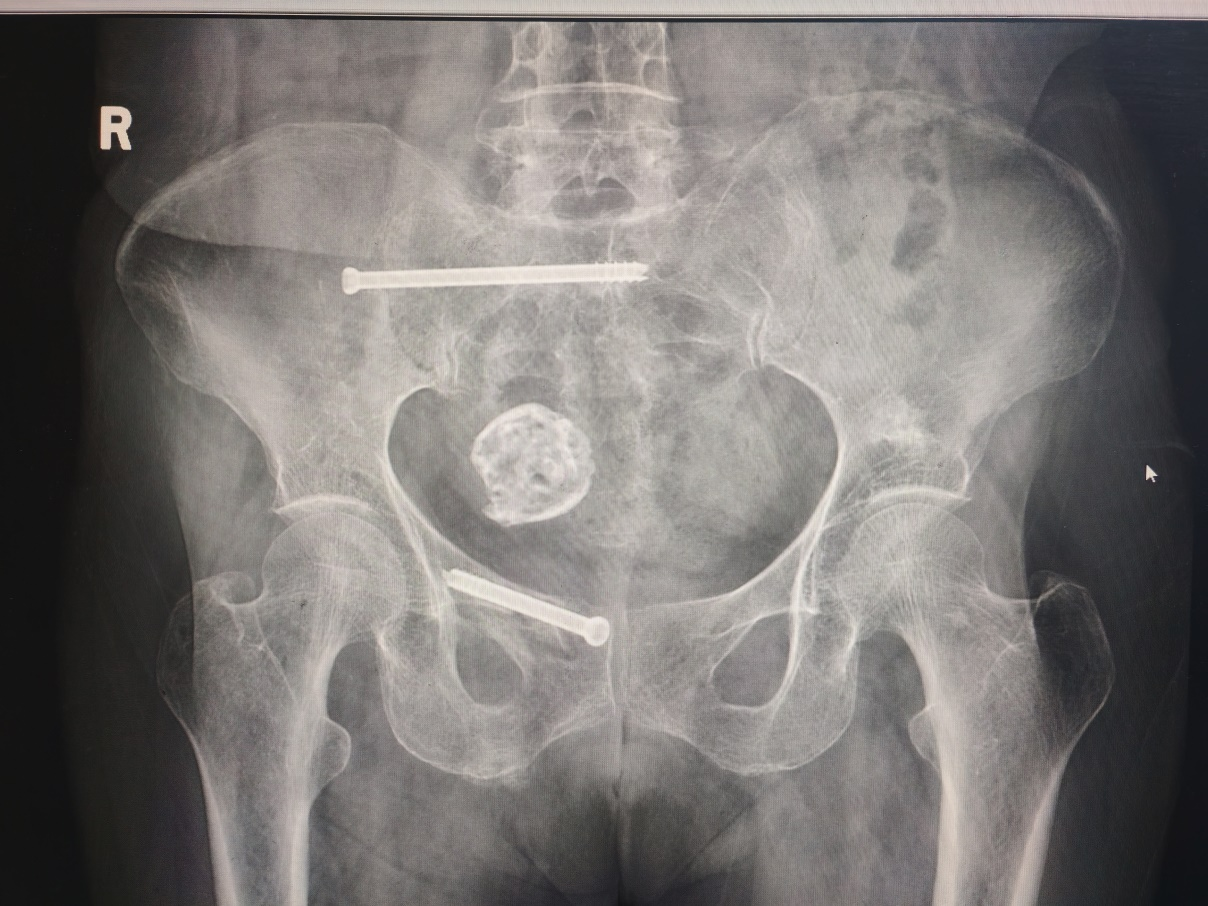

李集丞主任在我院率先开展骶髂螺钉技术,致力于解决老年患者骨盆脆性骨折问题,段奶奶术后(图2)疼痛立刻缓解,十分开心,晚上也能正常睡觉了。

图2:骶髂螺钉技术